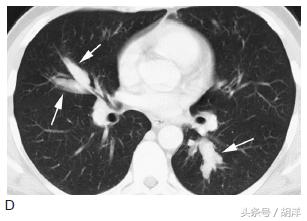

变态反应性支气管肺曲菌病

这种状态是身体本身为过敏体质,长期合并曲菌吸入,身体因为严重的过敏反应形成大量粘稠的粘液栓塞在气管中,很容易形成中央型支气管扩张,患者同时伴有哮喘样发作,很容易和哮喘混淆,但使用抗哮喘药物无效。

箭头所指为粘液栓和支气管扩张